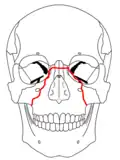

At the beginning of the 20th century, René Le Fort mapped typical locations for facial fractures; these are now known as Le Fort I, II, and III fractures (right).[7] Le Fort I fractures, also called Guérin or horizontal maxillary fractures,[14] involve the maxilla, separating it from the palate.[15] Le Fort II fractures, also called pyramidal fractures of the maxilla,[16] cross the nasal bones and the orbital rim.[15] Le Fort III fractures, also called craniofacial disjunction and transverse facial fractures,[17] cross the front of the maxilla and involve the lacrimal bone, the lamina papyracea, and the orbital floor, and often involve the ethmoid bone,[15] are the most serious.[18] Le Fort fractures, which account for 10–20% of facial fractures, are often associated with other serious injuries.[15] Le Fort made his classifications based on work with cadaver skulls, and the classification system has been criticized as imprecise and simplistic since most midface fractures involve a combination of Le Fort fractures.[15] Although most facial fractures do not follow the patterns described by Le Fort precisely, the system is still used to categorize injuries.[5]

| Le Fort II fractures | |